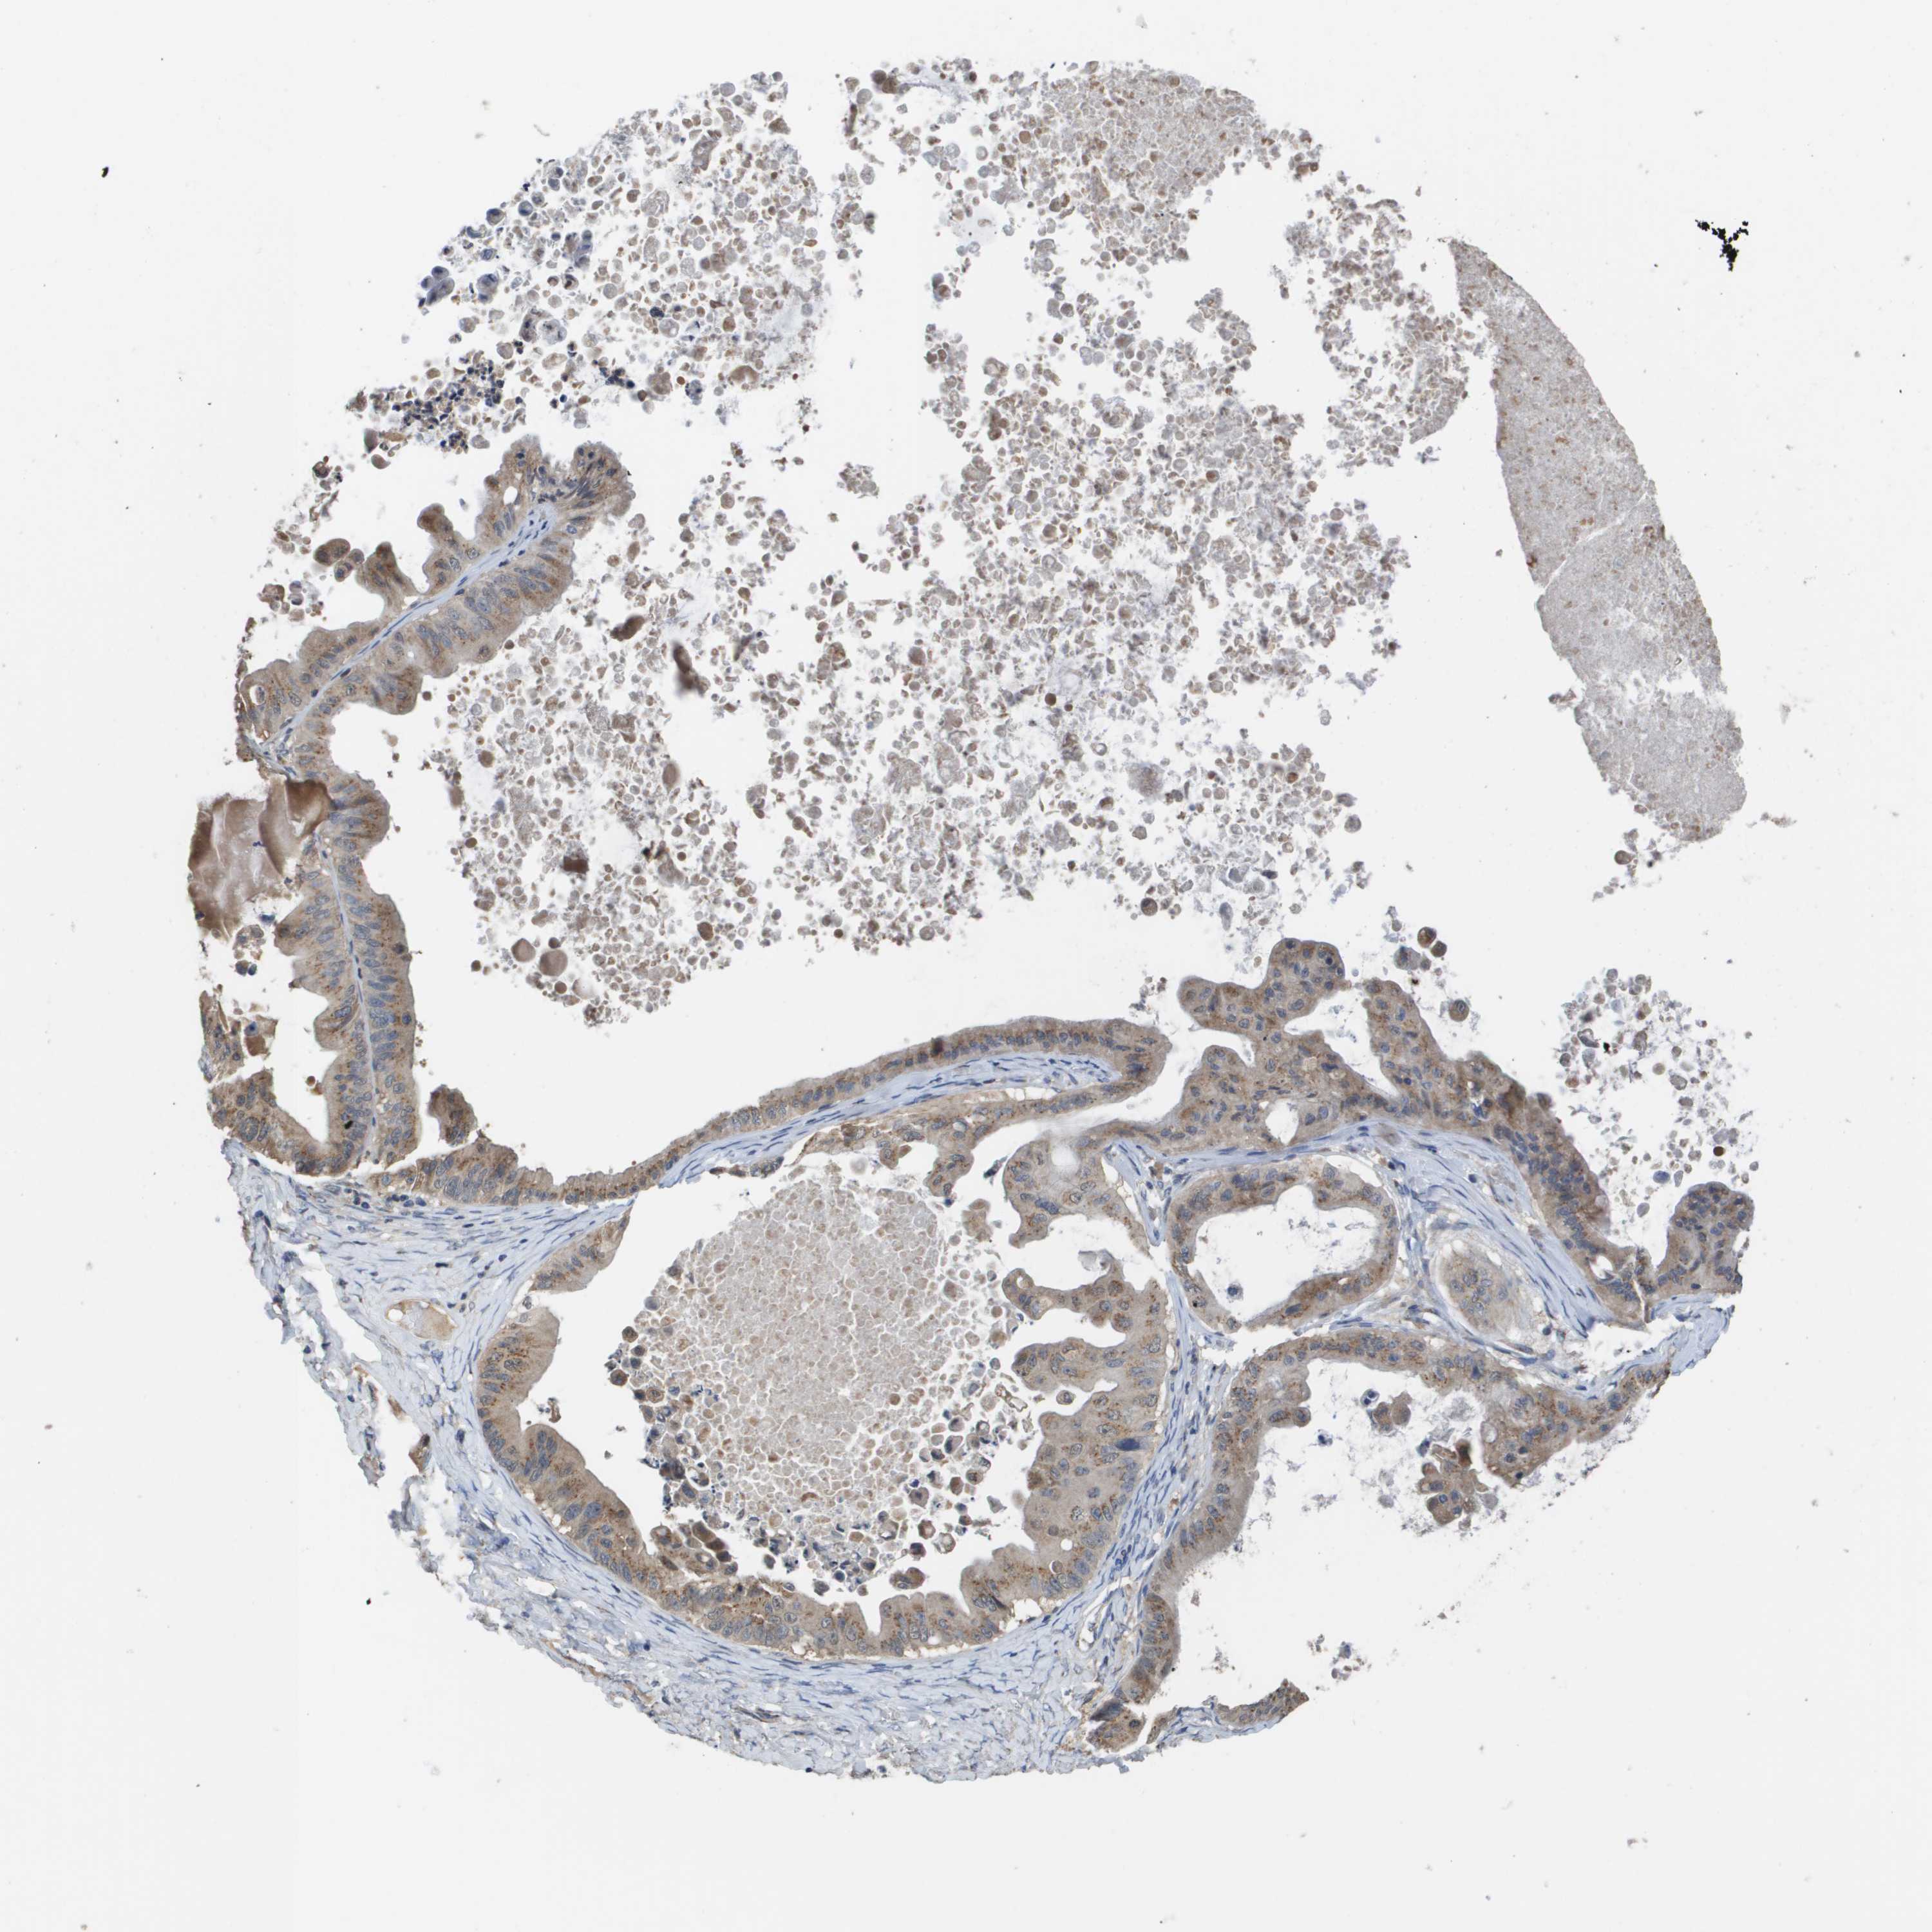

OVARIAN CANCER - Protein expressioni

A mouse-over function shows sample information and annotation data. Click on an image to view it in a full screen mode. Samples can be filtered based on level of antibody staining by selecting one or several of the following categories: high, medium, low and not detected. The assay and annotation is described here.

Note that samples used for immunohistochemistry by the Human Protein Atlas do not correspond to samples in the TCGA dataset.

Antibody stainingi

Antibody staining in the annotated cell types in the current human tissue is reported as not detected, low, medium, or high, based on conventional immunohistochemistry profiling in selected tissues. This score is based on the combination of the staining intensity and fraction of stained cells.

Each image is clickable and will lead to virtual microscopy that enables deeper exploration of all samples and also displays staining intensity scores, fraction scores and subcellular localization as well as patient and tissue information for each sample.

Antibody HPA006277

Carcinoma, endometroid

Carcinoma, NOS